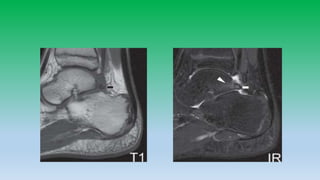

5. T1 mid sagittal image shows sharp interface b/w the normal bright kagers fat pad and normal uniformly dark Achilles tendon. Mid sagittal inversion recovery image revales no abnormal signal intensity in Achilles. Whitw arrow head shows normal fluid present in retrocalcaneal bursa.